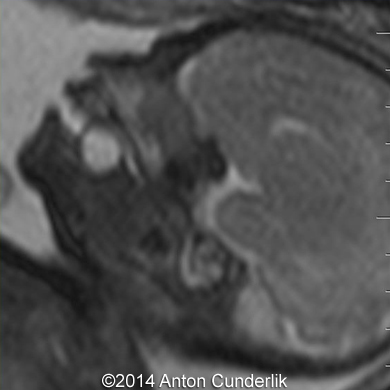

Image 8, 9, 10: 33 weeks of gestation; MRI images showing the cystic structure within the fetal tongue representing thyroglossal cyst.

Fig09b

Fig10b

Fig08